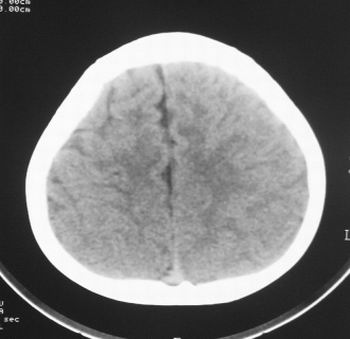

患儿,男,8岁,外伤2小时,无恶心、呕吐,四肢活动正常。既往无任何不适,智力发育正常。

典型的左中颅窝蛛网膜囊肿。

典型的左中颅窝蛛网膜囊肿。最常见的发病部位,张力比较高,相应颅板受压变薄。赶紧治疗,脑组织的功能可能部分恢复。